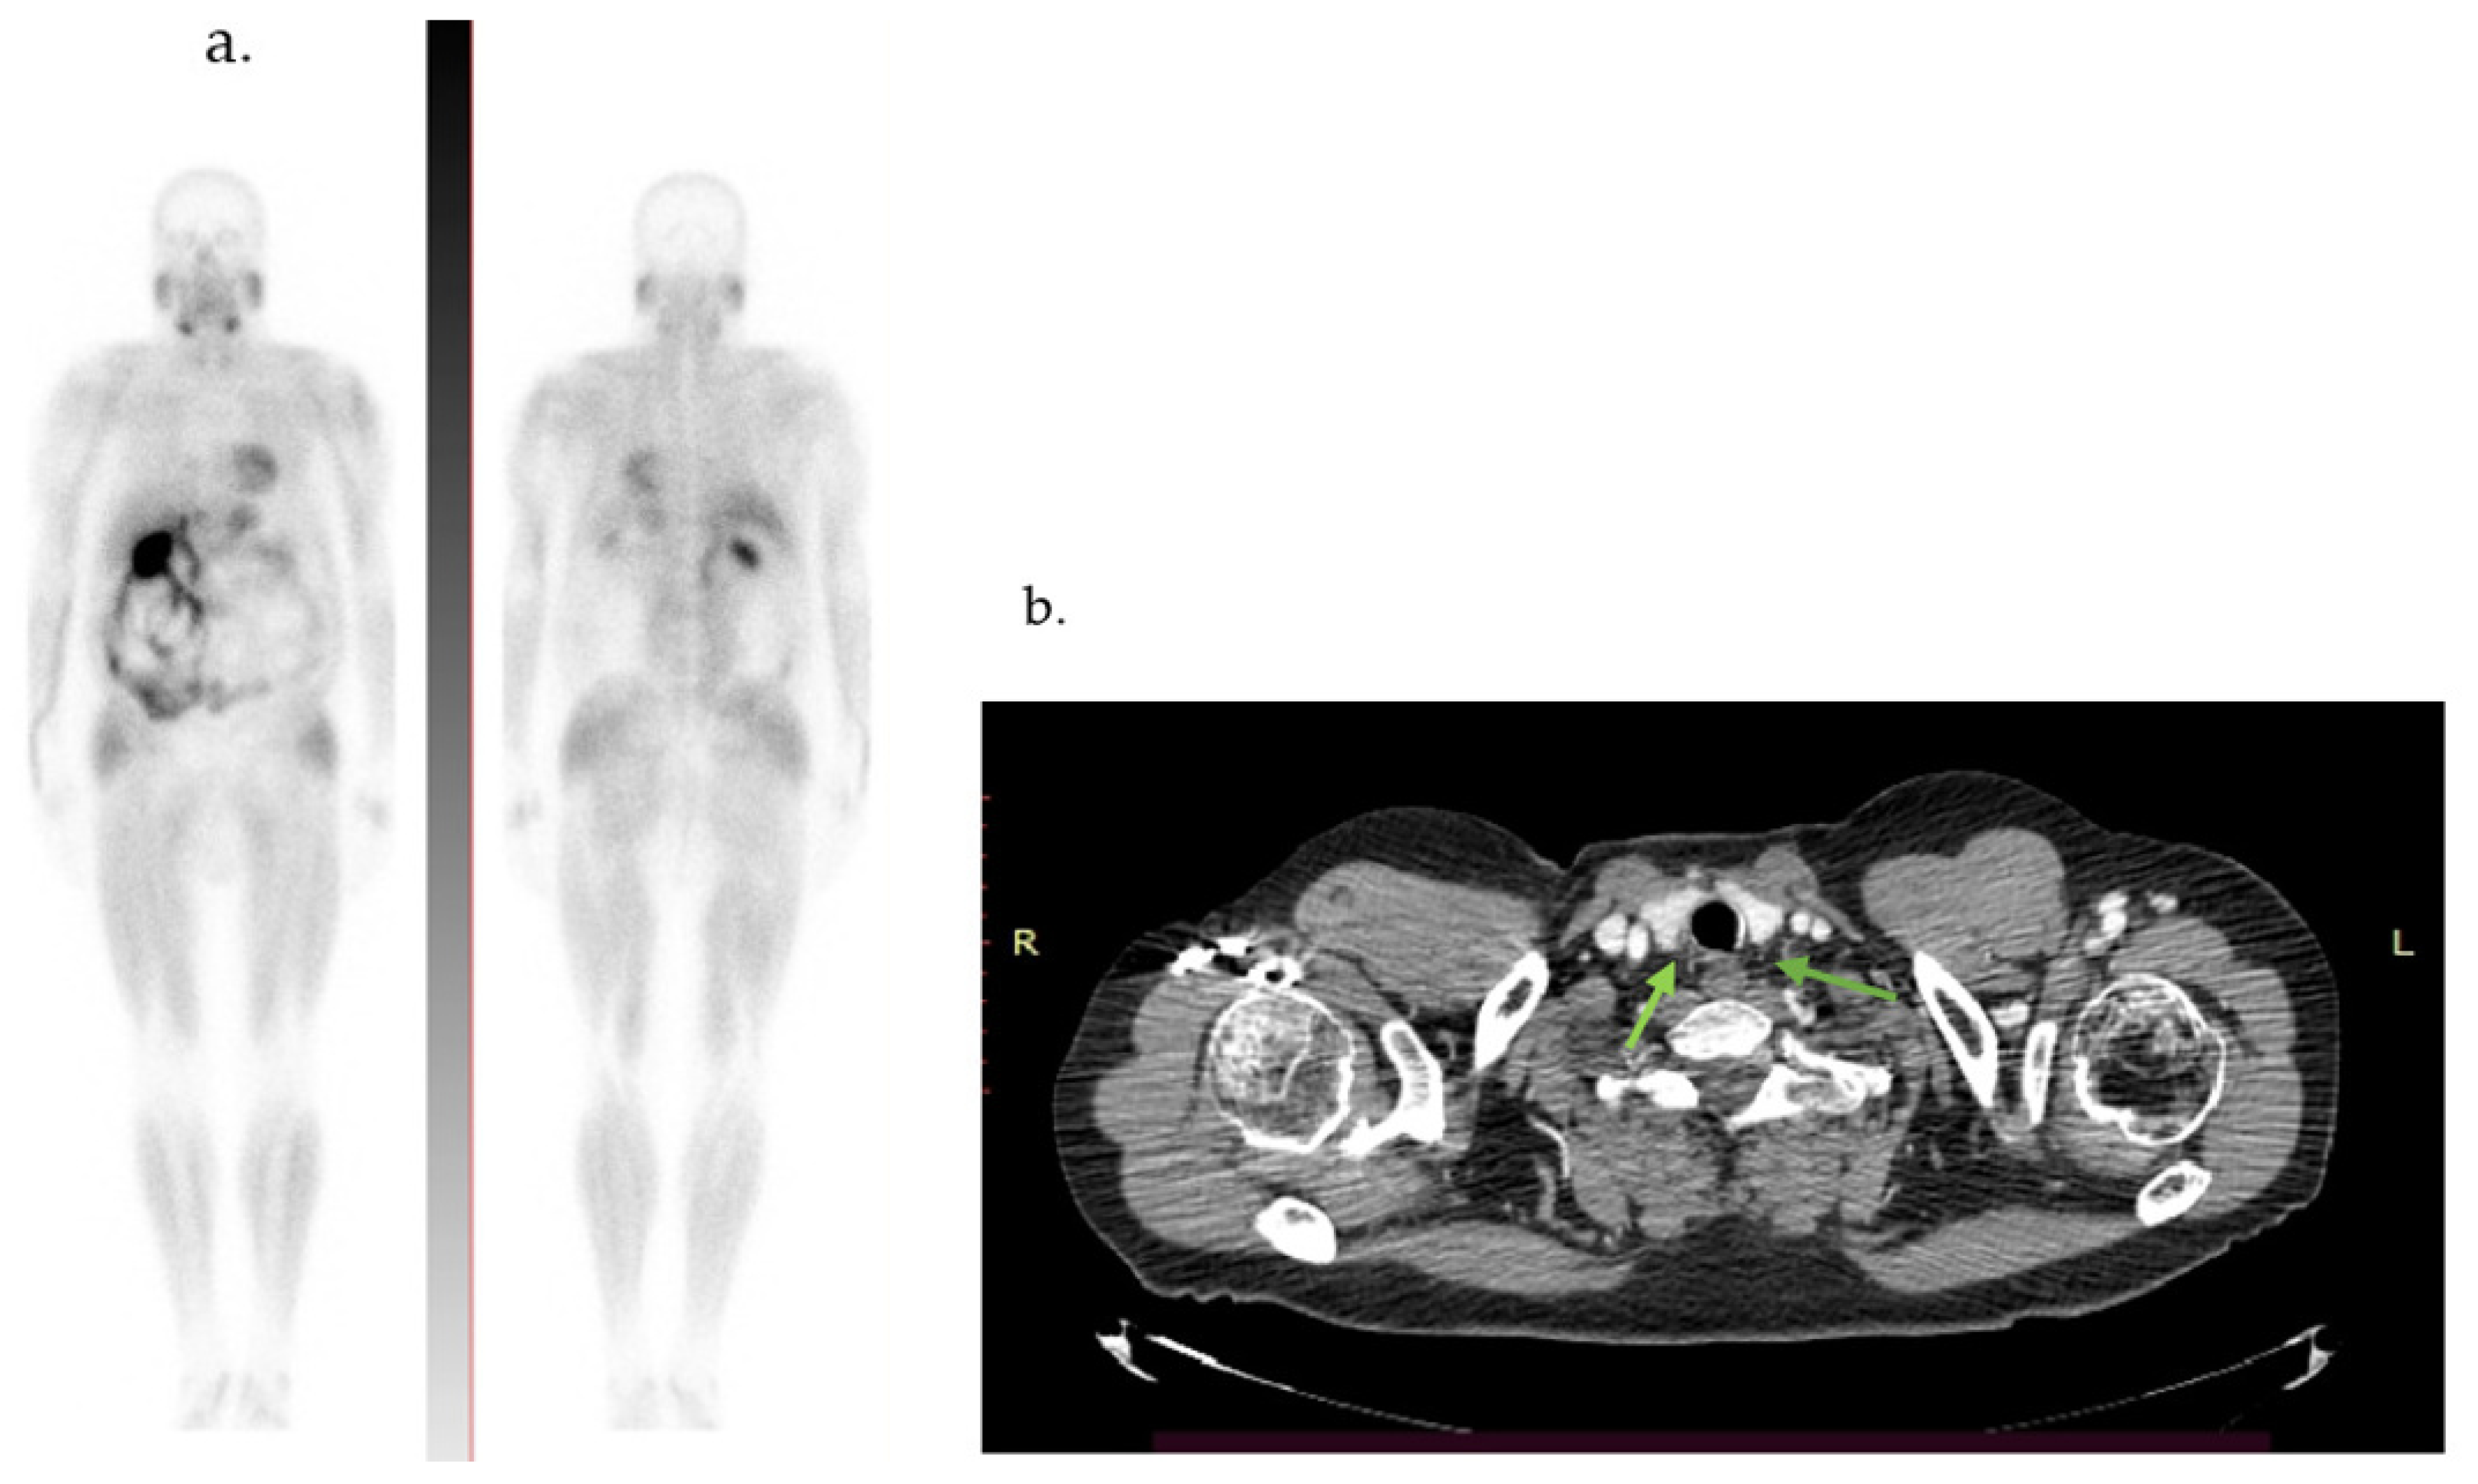

2.2. Case 2